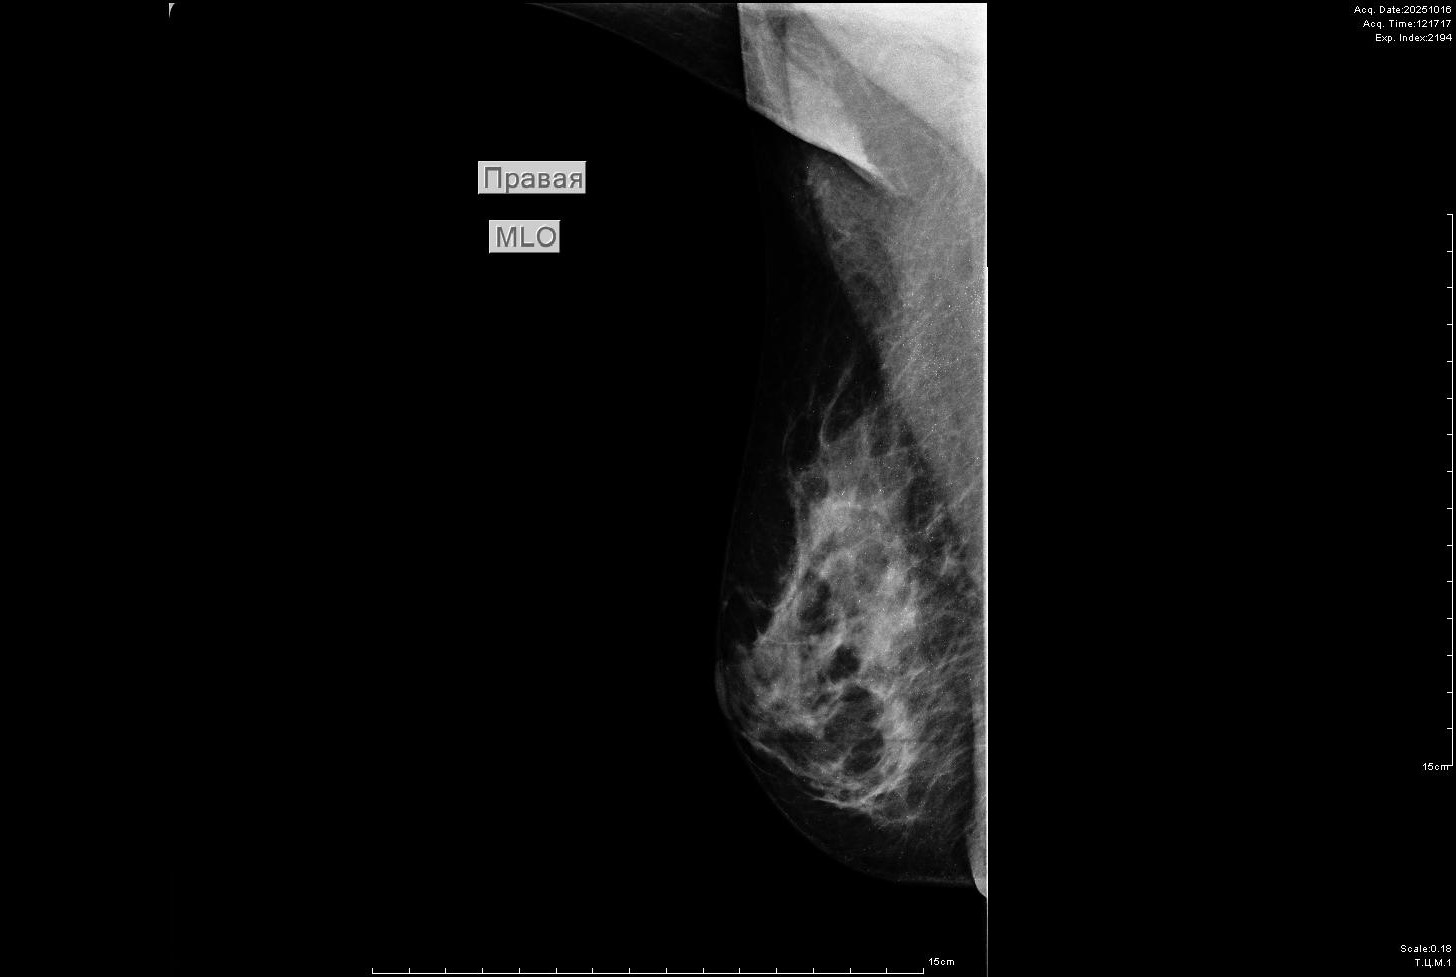

Расшифруйте, пожалуйста, маммографию. Вот что было в выданном заключении: Рентгенологическая картина стромы симметричная, тип плотности тканей молочных желез по ACR "С", гетерогенной плотности. Точечные кальцинаты. Тени единичных мелких кист. Объемных образований, мелкозернистых кальцинатов и лучистых изменений не определяется. BI-RADS 2 справа,  BI-RADS 2 слева.

Заключение: Рентгенологическая картина типа строения по ACR "С".

Пугают кальцинаты, и они толком не описаны никак. На снимке все в мелких крупицах и ворсинках - для обывателя выглядит страшно. Стоит ли обследоваться дальше, что именно рекомендуется сделать?

Возраст? Согласен с описанием. Мелкие кальцинаты не представляют опастности. Для самоуспокоения, можно ещё пройти УЗИ молочной железы, поведение этих 2-х исследований практически гарнтия не пропустить что-то полохое- более эффективное,  пока не придумано, для скрининга рака молочной железы.

На предыдущих маммографих кальцинатов не находили. А в этот раз нашли и их так много, как мукой обсыпано. Это не требует в будущем как-то более внимательно наблюдать?

Диффузное и двухстороннее распределение (точечных) кальцификатов характеризуется как доброкачественное.